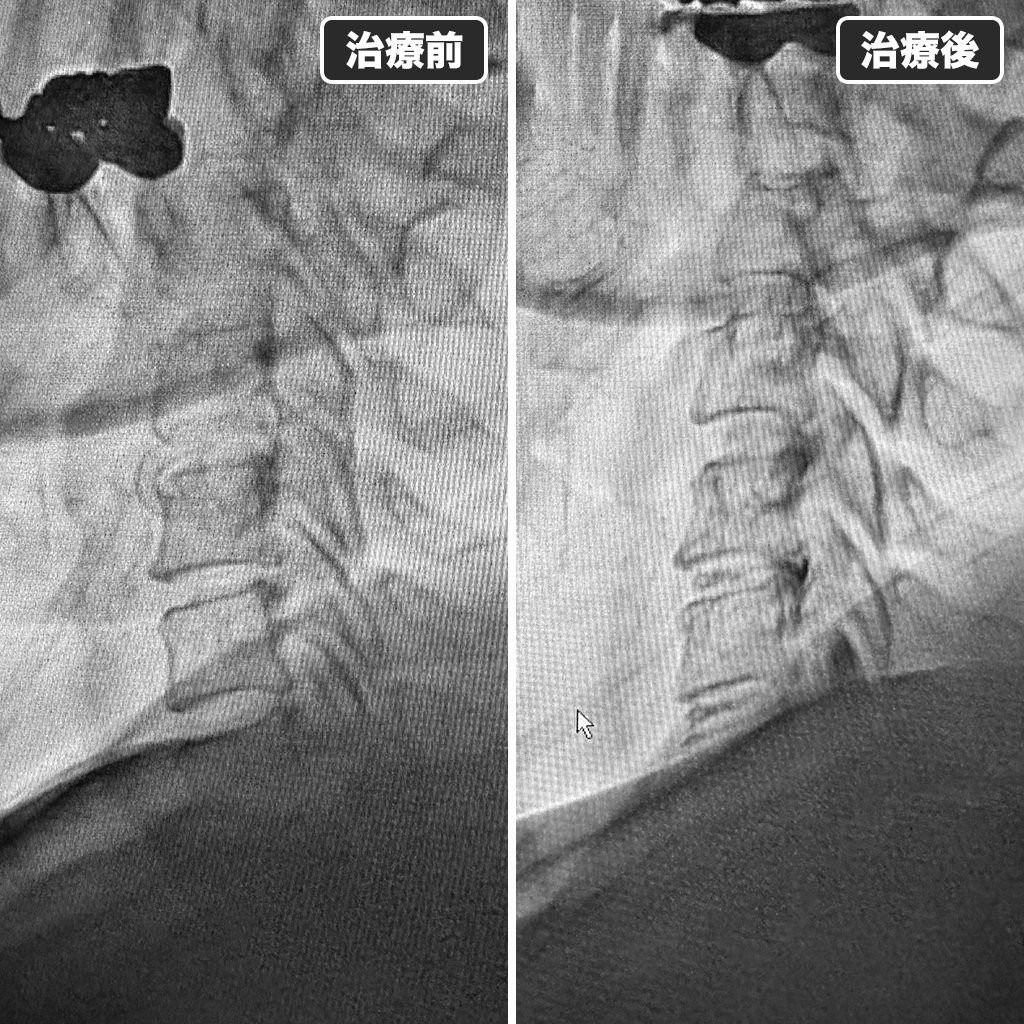

治療前後のレントゲン写真

治療前後のレントゲン写真になります。左側が治療前で右側が治療後になります。治療時間は18分程でした。鎮静剤を使用しますので痛みも不安も感じられることはありませんでした。